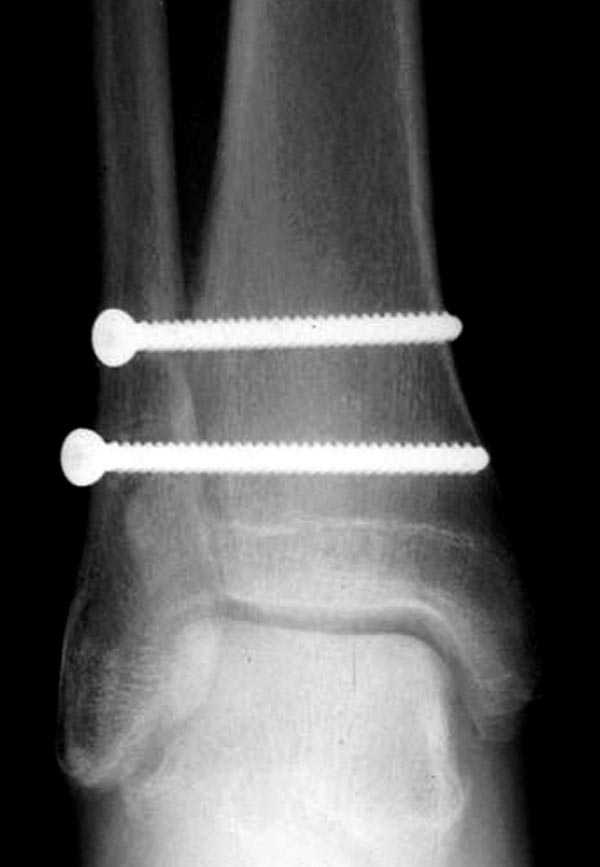

Две параллельных шурупа создают условия для сращения мембраны и синдесмоза, 8 недельный срок достаточен, и можно удалить фиксаторы.

В случае, если это подтвердиться надо оперироват, как показал Джолдас.

Глубокоуважаемый Якоб Одесскиий! Увы, но из снимков голеностопа возможно предоставить только приложенный, боковая проекция в первичном сообщении. Спасибо за указание возможного повреждения голеностопа, но напомню, что главный вопрос топика о неоходимости синтеза малоберцовой кости ПЛАСТИНОЙ. В примерах показанных Джолдасом Кульджановым пластина и вообще вмешательство в область перелома не используется, т.е. его позиция ясна. Вы можете что-то добавить?